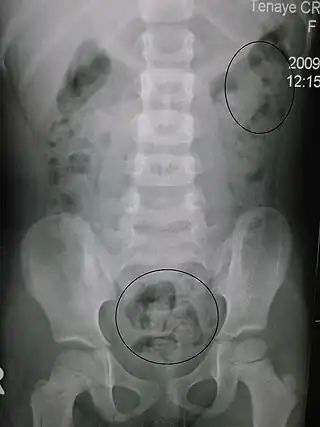

![]() Estreñimiento visto a través de rayos X. Los círculos representan áreas de materia fecal (las heces están rodeadas de blanco debido al gas de los intestinos). | ||

Las radiografías del abdomen, por lo general solo se realizan si se sospecha obstrucción intestinal que puede revelar materia fecal retenida en el colon, y confirmar o descartar otras causas de síntomas similares.